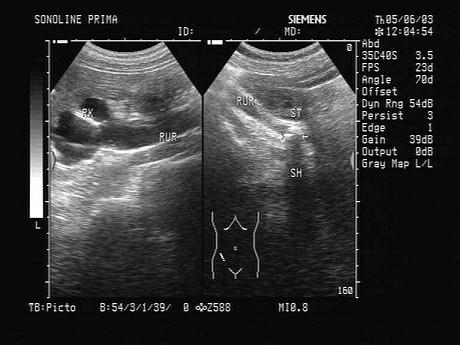

结合超声图像,肾脏积水最常见的原因是?(?)A.输尿管结石B.输尿管囊肿C.输尿管肿瘤D.输尿管脱垂E.输尿管先天畸形

问题 结合超声图像,肾脏积水最常见的原因是?(?)

选项 A.输尿管结石 B.输尿管囊肿 C.输尿管肿瘤 D.输尿管脱垂 E.输尿管先天畸形

答案 A